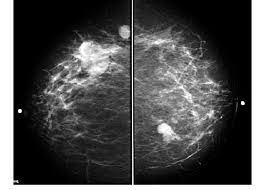

Generally speaking, the denser the tissue, the whiter it appears. These deposits show up as tiny white spots on a mammogram, and there may be only one or two, or too many to count, says jay baker, md, a breast imaging specialist at the duke cancer center.most people assume that what doctors are looking for on a mammogram are lumps, dr. Not all women have calcifications in their breasts—but most do. A mammogram image has a black background and shows the breast in variations of gray and white. Rate of dcis discovery is increasing, due to screening mammograms. If microcalcifications are found on your mammogram, the radiologist will do the following to help determine what if anything needs to be done: What does breast cancer look like? If you have calcifications, they'll show up as white spots. Generally, whiter mammogram images indicate denser breasts. This can make it harder for your radiologist to spot signs of breast cancer, since dense tissue and tumors both look white in mammogram images. However, a mammogram is not perfect and it is difficult to detect abnormalities in a person with dense breasts. People should become familiar with the typical look and feel of their. It's common to have dense breasts.

The person having the mammogram will place their breast between … However, cancer can also be seen as white, making it a bit obscure in women with extremely dense breasts. They can vary greatly from painful, hard, and immobile to soft, painless, and easily moveable. Specialist doctors (radiologists) trained to interpret mammograms can identify any abnormal areas, masses or calcium. So, an ultrasound is typically a 'second look' type of application.

Screening mammograms have been used since the 1980s. It can be hard to know from a mammogram image whether the cluster is dcis or invasive breast cancer. A mammogram image has a black background and shows the breast in variations of gray and white. A mammogram can show breast changes such as calcifications, masses, or other symptoms that might be cancer.abnormalities such as cancerous tumors usually appear brighter because they are denser. This appears most commonly as streaking, known as linear enhancement. What does breast cancer look like on a mammogram? A breast mri captures multiple images of your breast. What does breast cancer look like on a mammogram?